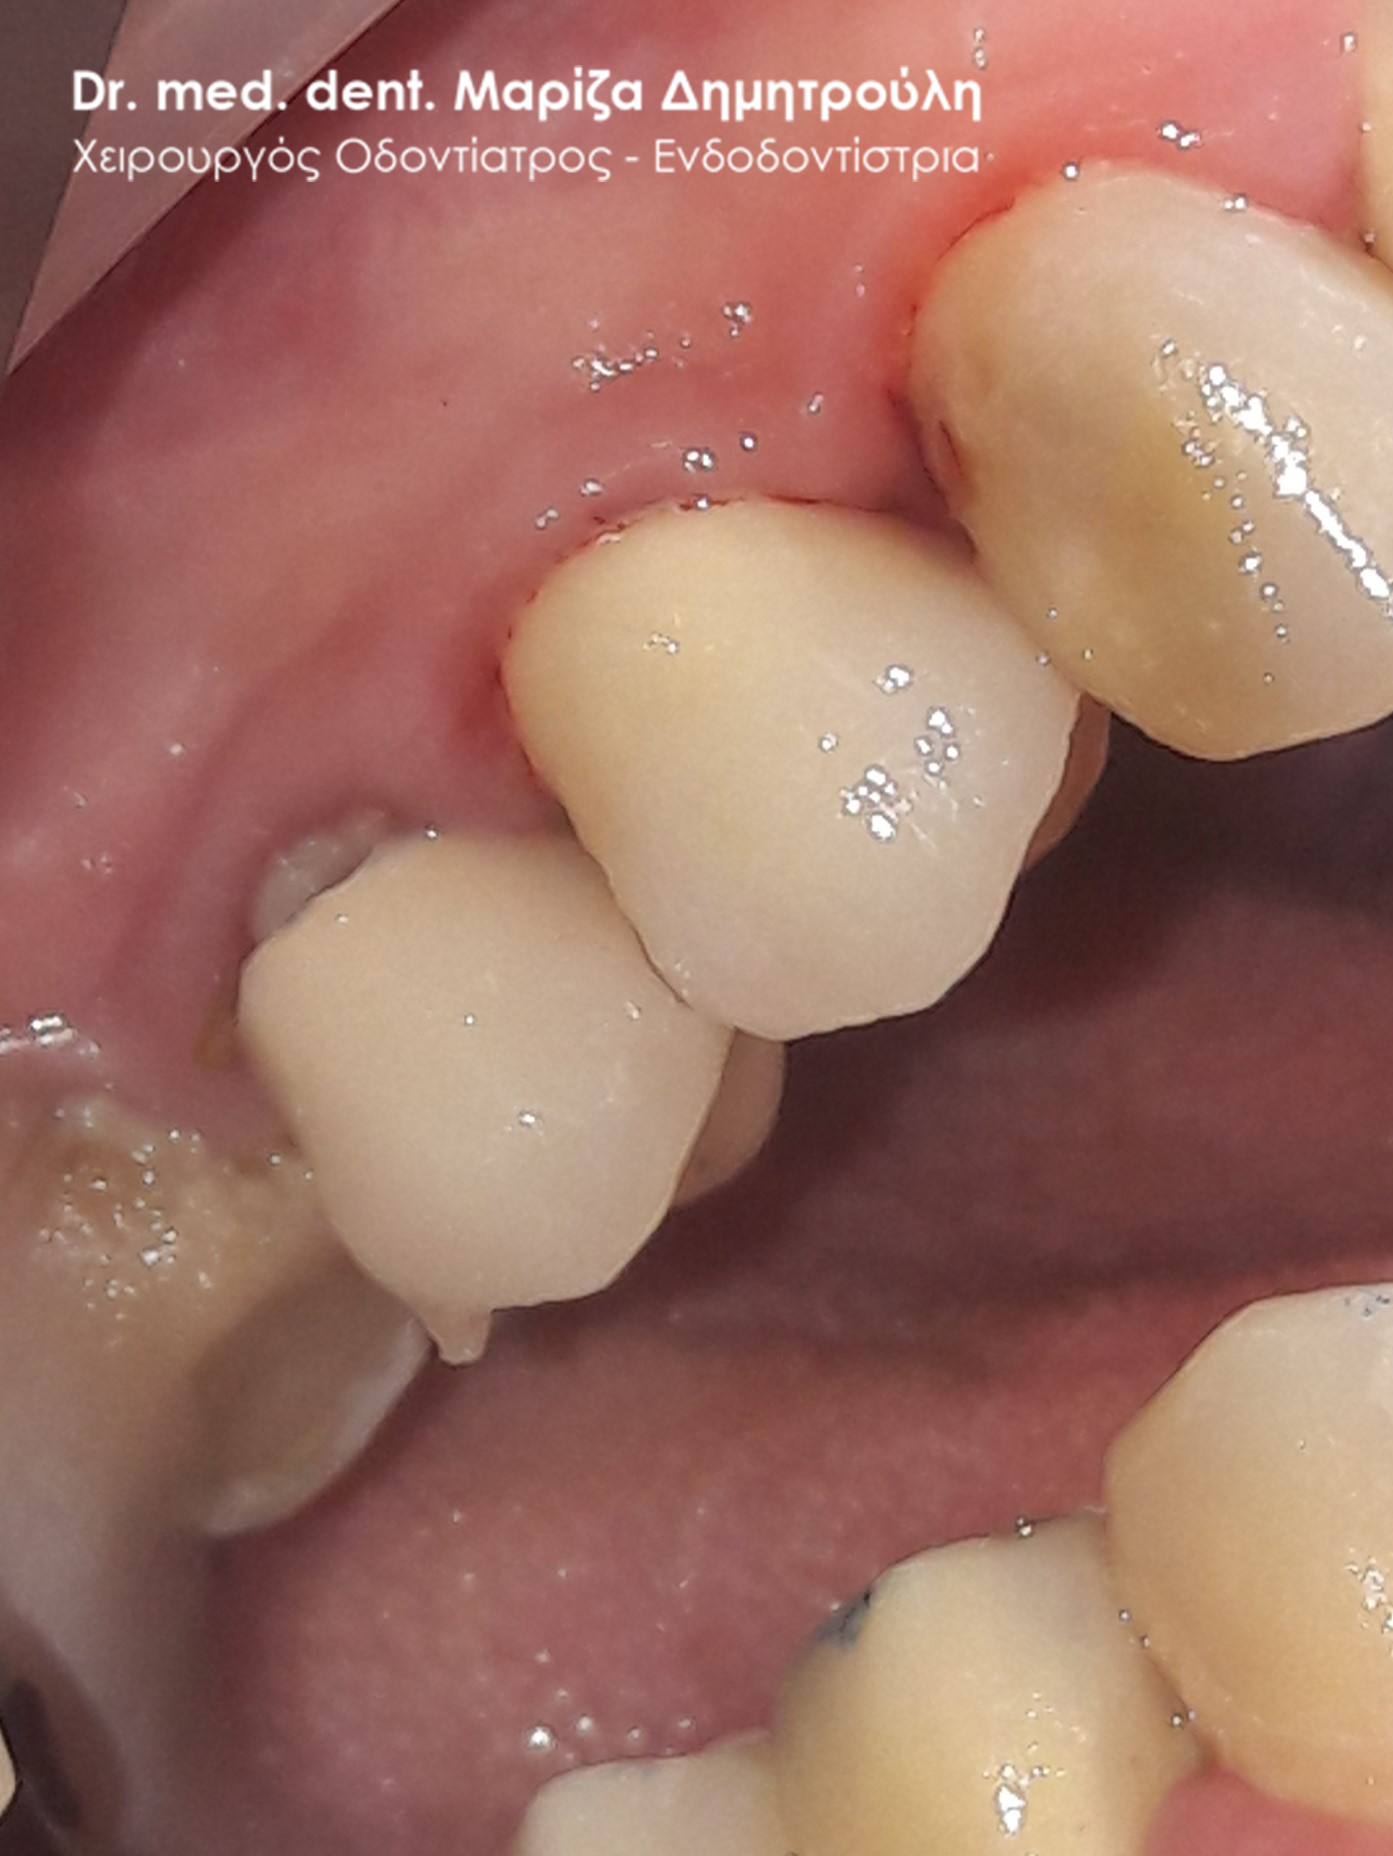

Περιστατικό – Ολοκεραμική στεφάνη / θήκη ζιρκονίου στον άνω αριστερό γομφίο

Η ασθενής επισκέφτηκε το ιατρείο μας γιατί πονούσε στον πρώτο άνω αριστερό γομφίο. Η κλινική και ακτινογραφική εξέταση φανέρωσε την αναγκαιότητα απονεύρωσης του δοντιού. Μετά το πέρας της ενδοδοντικής θεραπείας και εφόσον το οδοντικό έλλειμα ήταν μεγάλο, κρίθηκε απαραίτητη η προστασία του απονευρωμένου δοντιού με ολοκεραμική θήκη.

Τελική κλινική εικόνα με την ολοκεραμική θήκη δοντιού